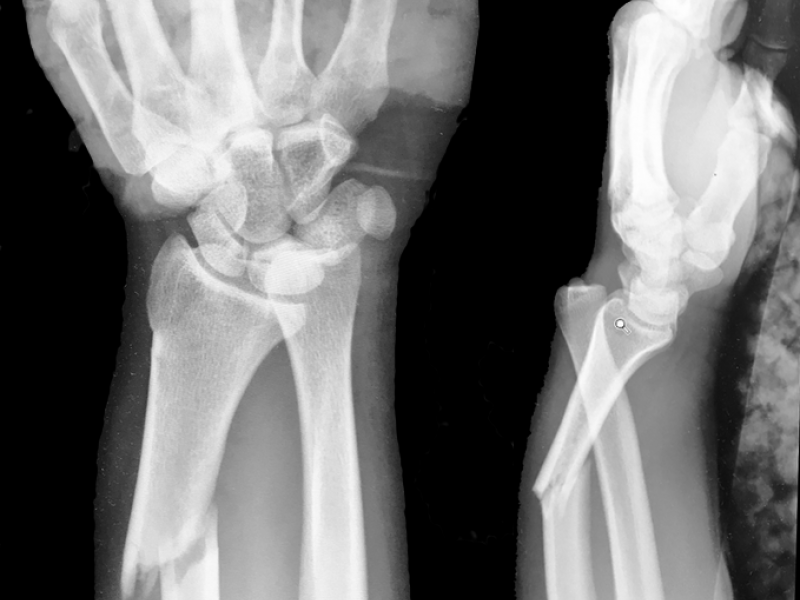

Patient fell on an outstretched hand and presents with arm